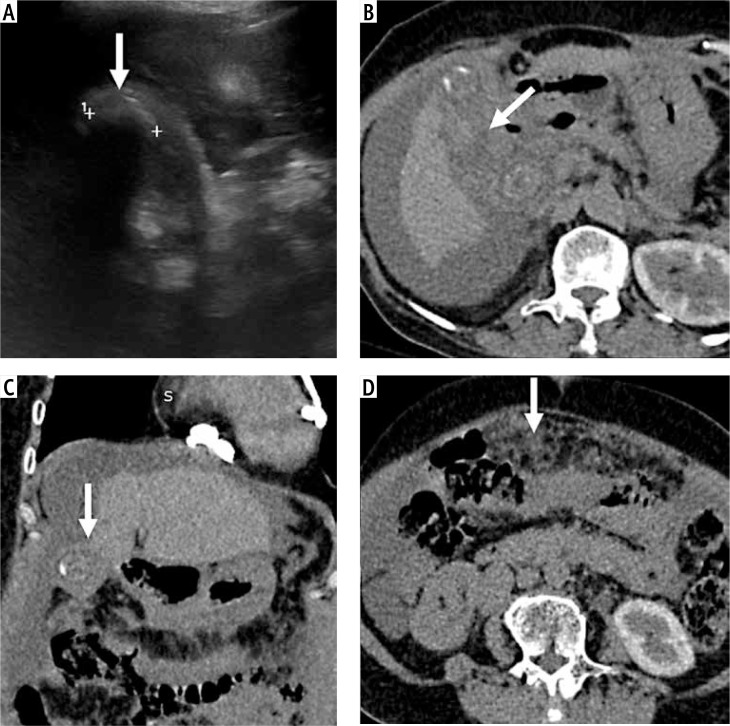

Material and methods: Consecutive patients with non-diagnostic US due to calculi within the gallbladder lumen, obscuring the detailed evaluation, were identified by a research fellow from a prospective database of patients with gallbladder lesions. The US reports and images were evaluated by a radiologist blinded to the final diagnosis. Patients who had the final pathological diagnosis based on fine-needle aspiration cytology, percutaneous or endoscopic biopsy, or surgical histopathology were included. Convolution neural networks (ResNet50, GBCNet), transformer models (vision transformer [ViT], RadFormer), and a hybrid model (MedViT) were trained on a public gallbladder dataset (GBCU dataset). The performance of these models for classifying gallbladder lesions into benign and malignant was tested on non-diagnostic (GB-RADS 0) US images.

Results: Training and validation cohorts (GBCU dataset) comprised 1004 and 251 images, respectively. The testing data (26 patients, mean age [SD]: 57.5 ±8.07 years, 17 female) comprised 304 images. The best performance for detection of GBC was achieved with GBCNet (sensitivity 51.1%, specificity 83.3%, area under the curve [AUC] 0.709) and MedViT (sensitivity 92.8%, specificity 50%, AUC 0.714). MedViT had the best accuracy (73.1%) for detecting benign gallbladder lesions.